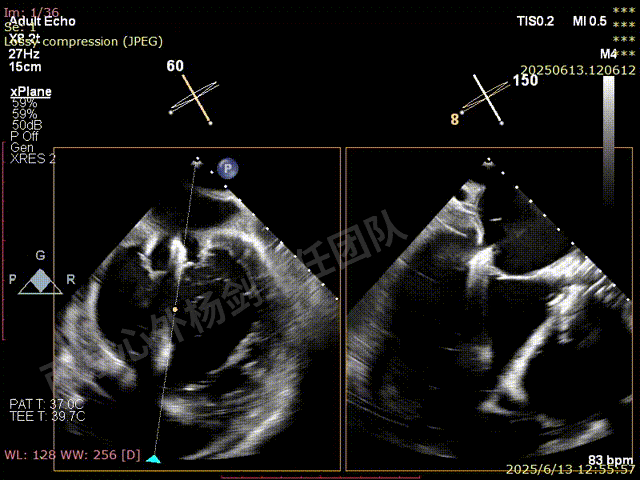

TEER术前超声评估

二尖瓣后叶栓系严重,前叶相对错位,反流束沿2区分布广泛,2偏3区处存在反流。

反流宽度至少23mm,因影像调整困难,考虑实际反流更宽。